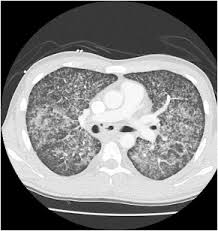

Ards caused by pulmonary and extrapulmonary disease: Therapy of acute respiratory distress syndrome: Ards nursing lecture (acute respiratory distress syndrome) with free quiz to help nursing students prep for nclex. Ards happens when the lungs become severely inflamed from an infection or injury. Ards, or acute respiratory distress syndrome, is a lung condition that leads to low oxygen levels in the blood. Learn about ards or acute respiratory distress syndrome. Home lung disease & respiratory health center topic guide. .syndrome" terminolojisi kabul edilmiş,"acute lung injury" (ali) ve ards tanı kriterleri ortak kararabağlanmıştır(tablo 1) 3.bu tarife göre ali, ards'nin erken safhası olarakgösterilmektedir. Acute respiratory distress syndrome (ards) with other comorbidities that eventually leads to death. Acute respiratory distress syndrome (ards) is an acute, diffuse, inflammatory form of lung injury that is associated with a variety of etiologies. Use of dynamic ct in acute respiratory distress syndrome (ards) with comparison of positive and negative pressure ventilation. Survey of german ards centers and scientific l. The main complication in ards is that fluid leaks into the lungs making breathing difficult or.

The Fibroproliferative Response In Acute Respiratory Distress Syndrome Mechanisms And Clinical Significance European Respiratory Society

The Fibroproliferative Response In Acute Respiratory Distress Syndrome Mechanisms And Clinical Significance European Respiratory Society from erj.ersjournals.com

Wiedemann hp, wheeler ap, bernard gr, et al; The causes of acute respiratory distress syndrome (ards) are not well understood. Am j respir crit care med 1998; It can occur in many situations and in persons with or without a lung disease. Ards happens when the lungs become severely inflamed from an infection or injury. Ards, or acute respiratory distress syndrome, is a lung condition that leads to low oxygen levels in the blood. Acute respiratory distress syndrome (ards) is a form of acute lung injury and occurs as a result of a severe pulmonary injury that causes alveolar damage heterogeneously throughout the lung. Neuromuscular blockers in early acute respiratory distress syndrome. Acute respiratory distress syndrome (ards) occurs when fluid builds up in the tiny, elastic air sacs (alveoli) in your lungs. Acute respiratory distress syndrome (ards). Ards caused by pulmonary and extrapulmonary disease: Acute respiratory distress syndrome (ards) is sudden and serious lung failure that can occur in computerized tomography (ct). Acute respiratory distress syndrome (ards) with other comorbidities that eventually leads to death.

This lecture will cover ards. Definitions of acute lung injury (ali) and acute respiratory distress syndrome (ards) have varied over time. A survey of academic intensivists' use of neuromuscular blockade in subjects with ards. The berlin definition of ards: Acute respiratory distress syndrome (ards) is a rapidly progressive disease occurring in critically ill patients. Ards was first described by ashbaugh and petty in 1967 in a case series of 12 icu. Ards can be life threatening. Learn about ards or acute respiratory distress syndrome. The inflammation causes fluid from nearby blood vessels to leak into the tiny air sacs in your. Survey of german ards centers and scientific l. Ards caused by pulmonary and extrapulmonary disease: Acute respiratory distress syndrome (ards) with other comorbidities that eventually leads to death. Ards, or acute respiratory distress syndrome, is a lung condition that leads to low oxygen levels in the blood.